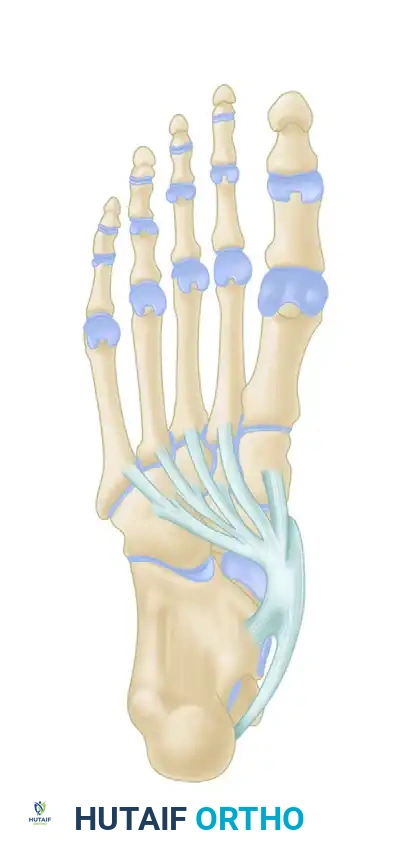

The collapse of the medial arch is rarely isolated to the tendon alone. As the PTT attenuates, increasing pressure and strain are transferred to the static medial restraints.

1. Spring Ligament Complex: The plantar calcaneonavicular (spring) ligament is the most commonly involved secondary restraint. Its attenuation allows the talar head to plantarflex and rotate medially.

2. Deltoid Ligament: In severe cases, the superficial deltoid ligament (specifically the tibionavicular portion) elongates, introducing significant medial ankle instability.

3. Plantar Fascia and Midfoot Ligaments: The naviculocuneiform and plantar metatarsal ligaments eventually fail, leading to fixed forefoot abduction and supination.

The talus slides distally, medially, and plantarward with the loss of the posterior tibial tendon and subsequent insufficiency of the plantar calcaneonavicular (spring) ligament.